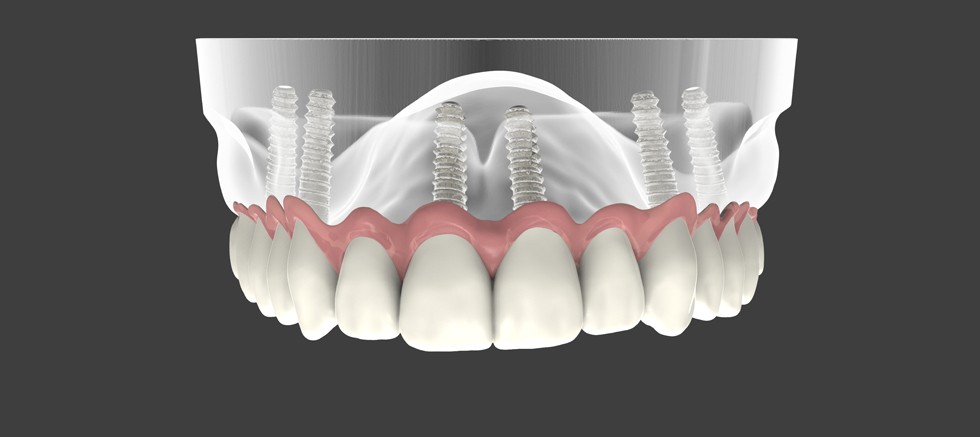

Eksik dişler gülüşünüz üzerinde en belirgin etkiye sahiptir. Diş eksiklerini tamamlamak, gülüşünüzü daha çekici hale getirerek ve zamanla yüz görünümünüzü değiştirebilecek kemik kaybını önleyerek, gülümsemenize güç katar. Ayrıca bitişik dişlerin hizadan çıkmasını önler ve tam ısırma işlevini geri kazandırır.

Diş implantları, dişlerin köklerinden taç kısmına kadar tüm dişin yerini aldığı için eksik dişler için en iyi tedavi yöntemidir. Çene kemiğinize cerrahi olarak yerleştirildikleri için implantlar üstün stabilite sunar. Ayrıca, kemik sağlığını destekleyen ve genç bir görünümü korumanıza yardımcı olan çene kemiğini uyarır.